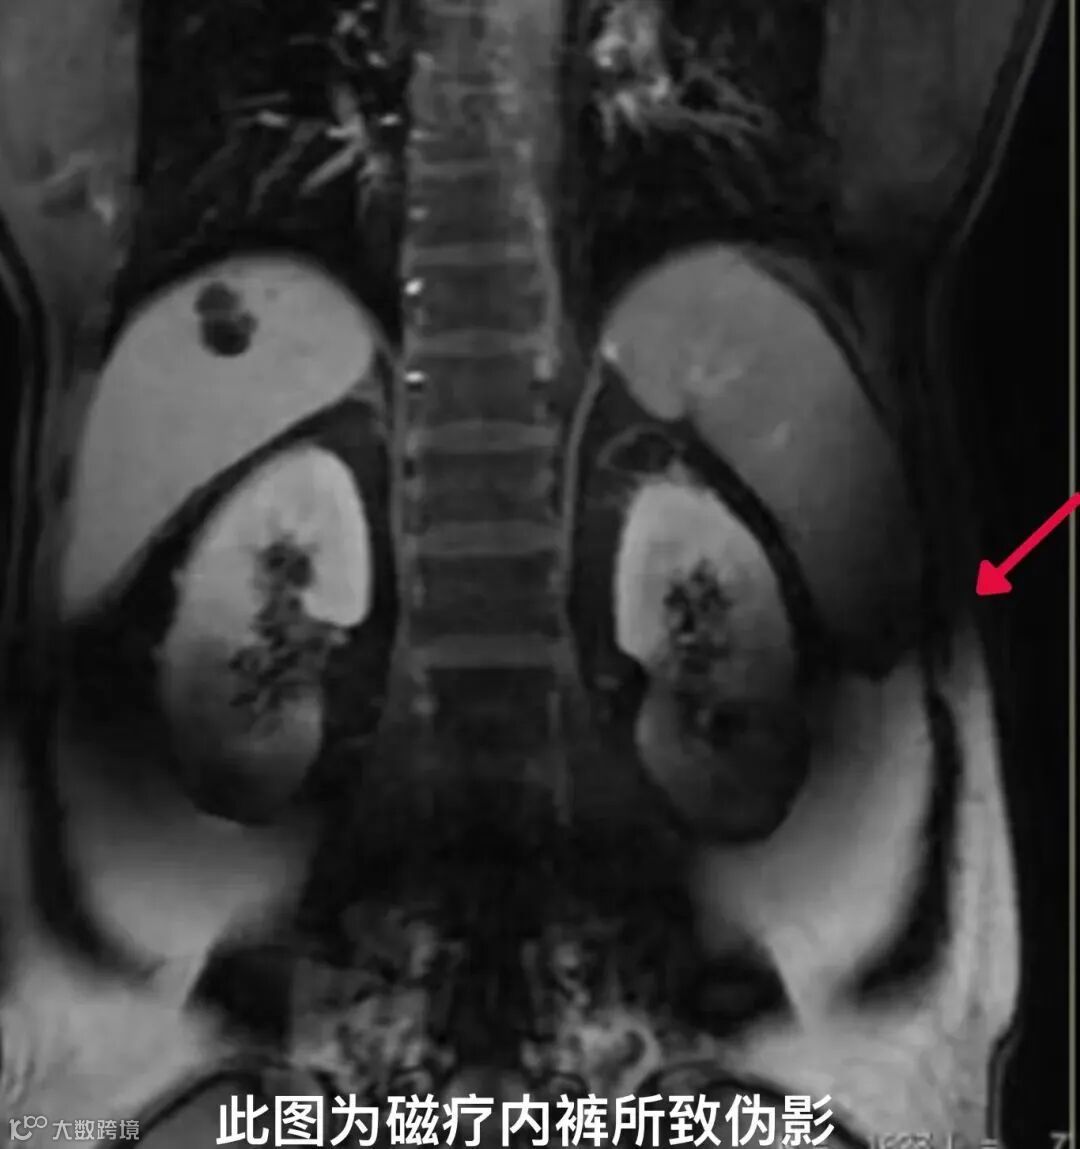

紧身瑜伽裤、磁疗内衣裤

很多人都知道做MRI检查不能带金属,但健身品牌会将金属纤维加入一些运动服装中,例如lululemon的瑜伽裤这类内嵌入银和铜纤维的纺织品,通过抗菌特性来控制气味,但如果穿这种含金属纤维的衣服做磁共振,检查过程中材料会升温,可能会导致接受检查的患者烧伤。

注意注意!穿lululemon瑜伽裤,请谨慎做磁共振检查!